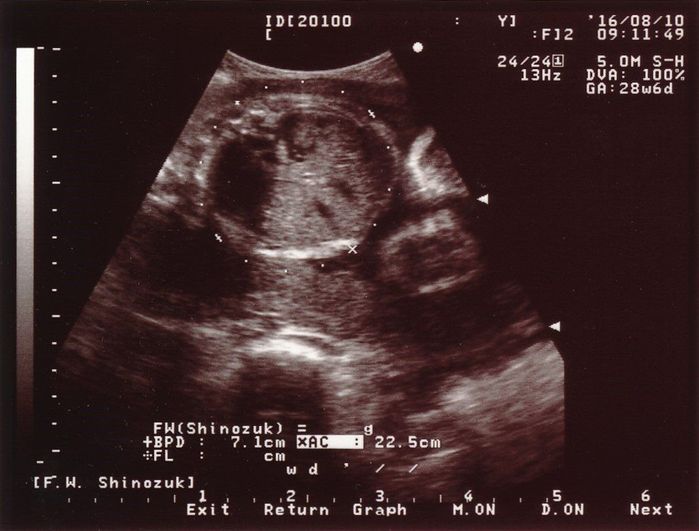

妊娠28週目のエコー写真

赤ちゃんの頭の大きさ(BPD)とお腹周り(AC)を測りました。赤ちゃんの成長は順調そのものでしたが、血液検査の結果で貧血の治療が必要となり、服薬はもちろんのこと、点滴のため週2回程度の病院通いが始まりました。

こちらは赤ちゃんのお尻の写真です。中央右寄り、お尻が上を向いていますので、頭が画面右下奥にあると思って見てください。女の子が確定した写真ですが、私の中では「やっぱり」という思いでした。